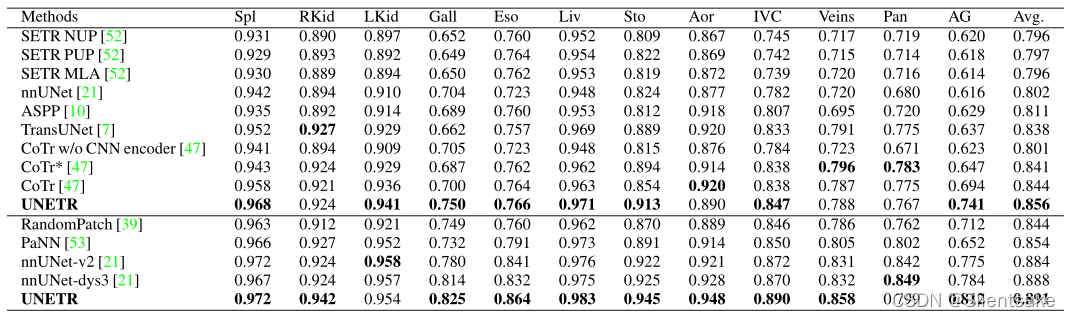

在BTCV排行榜上,UNETR在标准比赛和免费比赛中表现优于最先进的方法。如表1所示,在自由竞赛中,UNETR的整体平均Dice得分为0.899,比排名第二、第三和第四的方法分别高出1.238%、1.696%和5.269%。

表1:BTCV测试集的分割性能的定量比较。顶部和底部分别代表标准比赛和自由比赛的基准。作者的方法与当前最先进的模型进行了比较。

在标准竞赛中,比较了UNETR与CNN和基于Transformers的基线的性能。UNETR实现了一个新的最先进的性能与平均骰子得分85.3%在所有器官。在脾、肝、胃等大器官上,方法在Dice得分上分别比次优基线高出1.043%、0.830%和2.125%。此外,在小器官的分割中,在胆囊和肾上腺的Dice评分方面,方法显著优于第二最佳基线的6.382%和6.772%。

在表2中,在MSD数据集上比较了UNETR与CNN以及基于Transformers的方法在脑肿瘤和脾脏分割任务中的性能。在脑分割方面,UNETR在所有语义类上的平均表现比最接近的基线高出1.5%。特别是,UNETR在分割肿瘤核心(TC)分区域方面表现得相当好。同样,在脾脏分割方面,UNETR在Dice评分方面的表现比最佳竞争方法高出至少1.0%。

表2:定量比较了MSD数据集在脑肿瘤和脾脏分割任务中的分割性能。WT、ET和TC分别表示全肿瘤、增强肿瘤和肿瘤核心子区域。